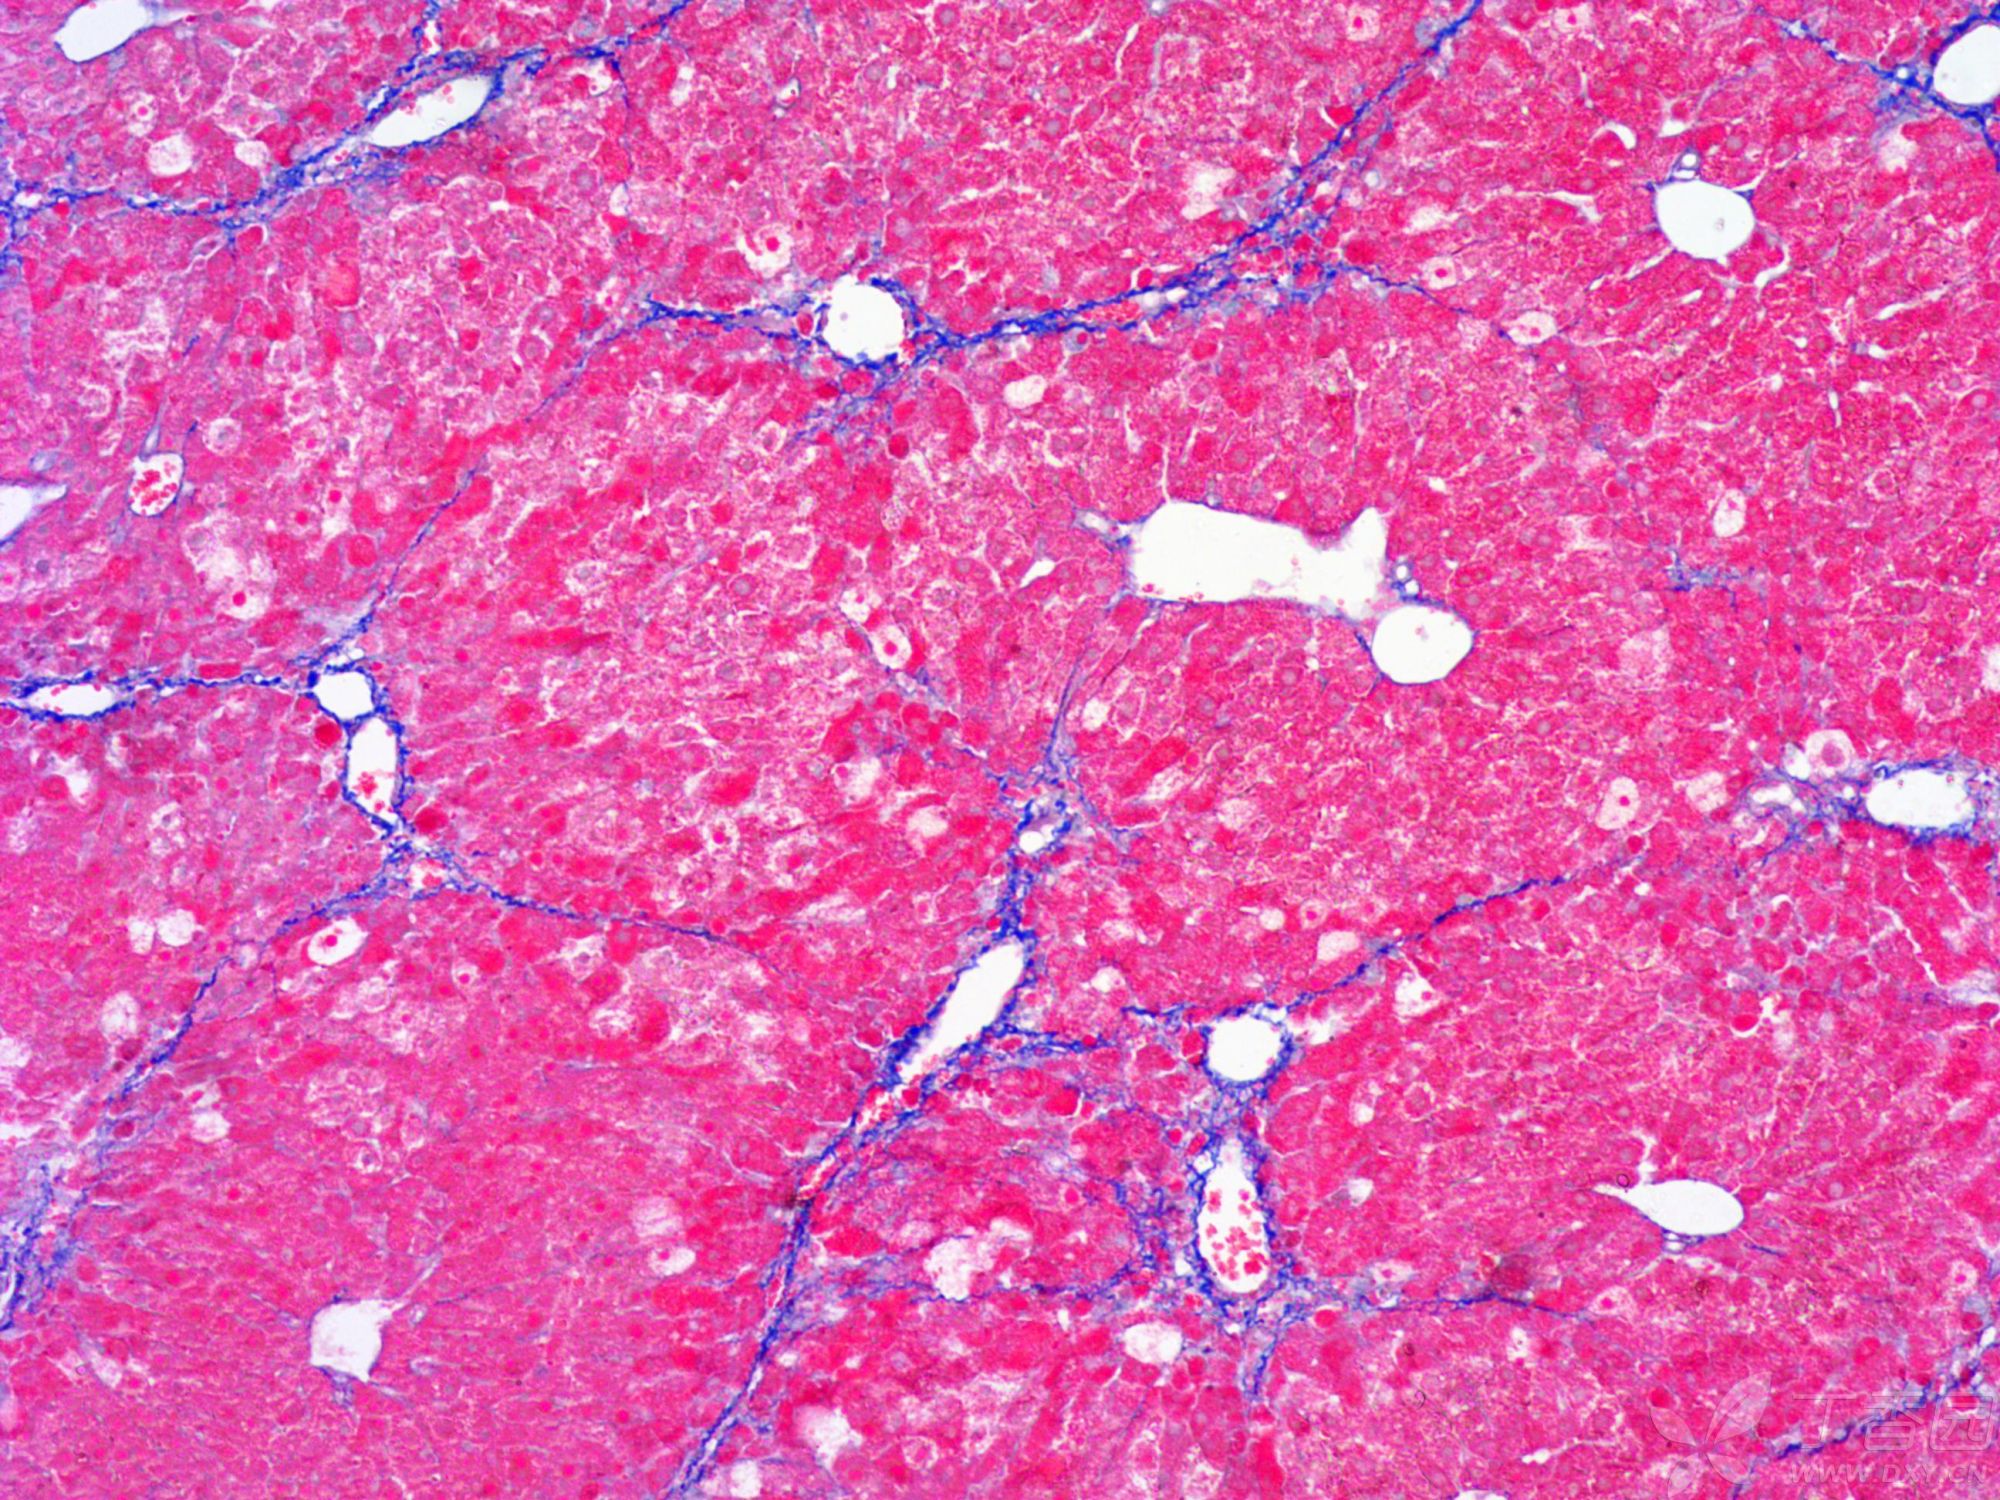

小鼠纖維化

MASSON染色的原理主要基于陰離子染料分子的大小和組織滲透性的關(guān)系。染料分子的大小決定了其能夠滲透進(jìn)入的組織類型。小分子量的染料能夠穿透結(jié)構(gòu)致密、滲透性低的組織,而大分子量的染料則只能進(jìn)入結(jié)構(gòu)疏松、滲透性高的組織。在MASSON染色中,由于肌纖維間隙較小,麗春紅等小分子染料能夠滲透其中并染色,使其呈現(xiàn)紅色;而膠原纖維間隙較大,大分子量的苯胺藍(lán)等染料能夠進(jìn)入并染色,使其呈現(xiàn)藍(lán)色或綠色。這種染色方式使得我們能夠清晰地觀察到并區(qū)分這兩種不同的組織成分。

Step9:使用苯胺藍(lán)或光綠液染色,使膠原纖維呈現(xiàn)藍(lán)色或綠色。